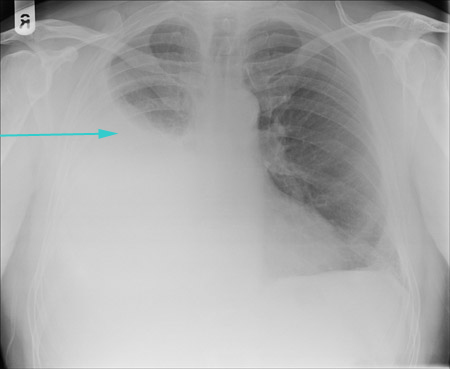

[Figure caption and citation for the preceding image starts]: CXR showing large right pleural effusionFrom the collection of Dr Kathryn Bateman; used with permission [Citation ends].